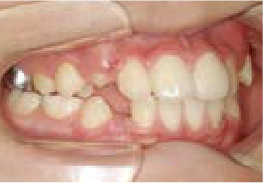

八重歯になっちゃった…歯が入る隙間がないけど、永久歯は抜きたくない!

Aさん (矯正開始時:9歳)

Before

After

すっきりしたお顔立ちの女の子ですが、外側から八重歯が生えてきてしまいました。

治療を終えて

マイオブレイスとBWS装置を使い、あごの骨や歯並びの形を整えながら、鼻呼吸や正しい飲み込み方も身に付けることができました。

お口の悪いクセは改善され、お子さん自身の力でしっかりとしたかみ合わせができるようになりました。ご希望通り永久歯を抜く必要はありませんでした。

主訴・治療内容 他院で「永久歯を抜いて矯正」をすすめられたが抜歯に抵抗があり「永久歯を抜かずに、あごの骨から整えてくれる」と口コミを見て当院を選んでくださいました。

治療期間 2年

費用 495,000円(税込)